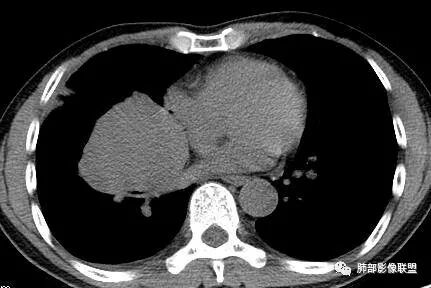

3.肿块常常较大,甚至巨大,病灶边界一般清楚,影像上常有假包膜样结构、有膨胀性生长的特点,影像科医师有时甚至会纠结其来源于肺部或是胸壁纵隔。常见的肺癌肿块,很少有机会能长成这样的规模。

4.边缘可以有浅切迹,部分病灶会有铸型样外观,但大体十分圆钝,不会出现典型的分叶和毛刺,也很少会出现胸膜牵拉。支气管常推移,有明显的支气管阻塞时也较少观察到相关的阻塞性炎症。

5.病灶密度大多不均,不规则坏死液化,少数病例出现钙化。增强扫描常观察到由外而内的厚壁不均匀强化,中央半岛样强化等等,厚壁中或实性区常能显示血管影。一些病灶中央呈现边界清楚囊样变。

6.病灶侵犯胸膜时可以出现胸水,病灶可以侵犯胸壁并引起相应临床症状。